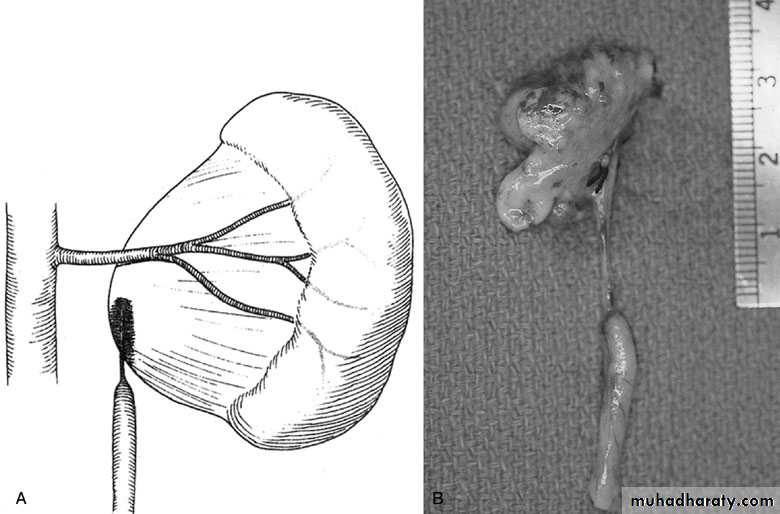

SURGICAL REPAIR including open surgical techniques, laparoscopic, & endoscopic approaches

Open & laparoscopic surgical techniques Anderson-Hynes dismembered pyeloplasty:

excision of the pathologic UPJ & appropriate

reanastamosis or flap technique or flap

operation

Nephrectomy

for non functioning kidney